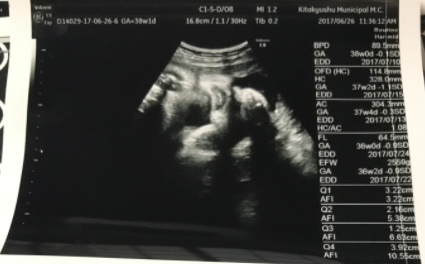

38週4日(38w4d・男の子)|きたうらりさ さん(27歳)

エコー写真撮影時のエピソード:

お腹も大きくなって食欲は増す一方で体重も増える一方。先生からは注意され頭も下がってきてないから頑張ってウォーキングしていた頃。パパとは離れていたので電話しながら色々話して楽しみにしてたなー。臨月にしてようやく初めてまともに顔がエコーで見れて嬉しかった。